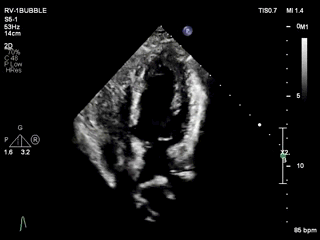

心脏CT:

膜周部室间隔缺损,伴随有膜部瘤形成;房间隔缺损;右位主动脉弓伴迷走左锁骨下动脉;Kommerell憩室;右位主动脉弓伴迷走左锁骨下动脉。